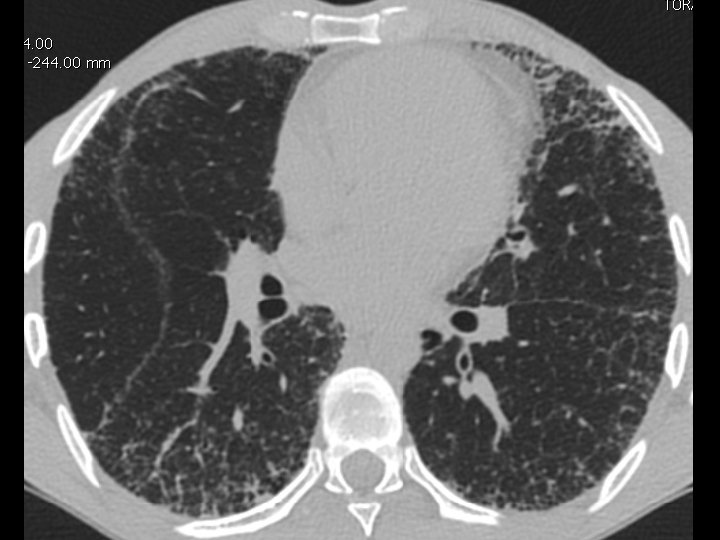

High-resolution CT scan

Subpleural, basal predominance Reticular abnormality Honeycombing with traction bronchiectasis UIPUIP Pattern

Subpleural, basal predominance Reticular abnormality Honeycombing with traction bronchiectasis Profuse micronodules UIPUIP Pattern Inconsistent with UIP Pattern

39 yo caucasian male, works in car collision repair and painting Multiple allergies, Gastroesophageal reflux disease and Thrombocytopenia of unknown etiology Smoker. No drugs CT: Reticular abnormality and honeycombing of subpleural basal predominance + micronodules Lung function tests: decreased diffusion capacity of the lung Blood tests: small increase of ESR and CRP; Autoimmune screening blood tests were normal BAL: normal celularity, with a mild increase in the neutrophil and eosinophil count

39 yo caucasian male, works in car collision repair and painting Multiple allergies, Gastroesophageal reflux disease and Thrombocytopenia of unknown etiology Smoker. No drugs CT: Reticular abnormality and honeycombing of subpleural basal predominance + micronodules Lung function tests: decreased diffusion capacity of the lung Blood tests: small increase of ESR and CRP; Autoimmune Screening Blood Tests were normal BAL: normal celularity, with a mild increase in the neutrophil and eosinophil count Definitive diagnosis can be established? Additional diagnostic tests required? Which tests?